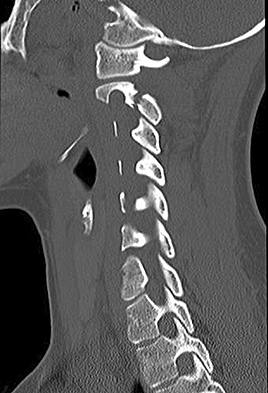

Figures 1 through 3 show the radiograph and CT images of a 68-year-old

woman who sustained a cervical injury after tripping over her cat. She has mild facial trauma, which includes a broken upper incisor and a nonsurgical nasal fracture. She is neurologically intact. Her past medical history is consistent with obstructive sleep apnea, non–insulin-dependent diabetes mellitus (hemoglobin A1c level of 9.0), and morbid obesity, with a body mass index of 40. What is the preferred treatment for this patient?

4. Anterior odontoid screw fixation Discussion: C

Posterior C1-2 fusion with instrumentation provides stability and pain relief with excellent clinical outcomes despite the loss of C1-2 motion. Hard collar immobilization and halo vest immobilization both carry a substantial risk of nonunion in this patient because of her age, fracture displacement, residual fracture gap, and medical condition. Anterior odontoid screw fixation theoretically preserves C1-2 motion. In this case, the fracture is not reduced. Concentric reduction is a requisite for osteosynthesis of the odontoid. Her body habitus also may not allow anterior odontoid fixation.